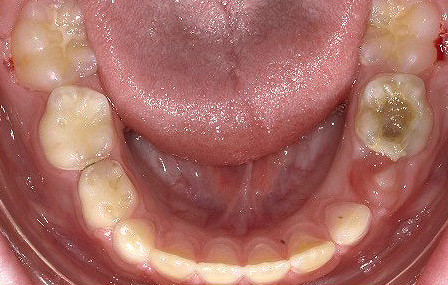

Klinisches Fallbeispiel 2 (Abb. 2a–y)

Distalbiss und tiefer Biss bei einem zwölfjährigen Mädchen. Die Behandlung erfolgte mit Invisalign und Precision Wings. Insgesamt waren zwei Schienensätze notwendig. Die Gesamtbehandlung dauerte 18 Monate.Bei der Planung des ClinCheck wurde der tiefe Biss vorwiegend über eine Intrusion der Unterkieferfront behoben, um die Lachlinie der Patientin nicht negativ zu beeinflussen. Die Oberkieferfront wurde nur retrudiert, jedoch vertikal nicht intrudiert. Während der Phase des Mandibular Advancement wurde die Wirkung der Precision Wings durch den Einsatz von Klasse II-Gummizügen unterstützt. Schlussendlich wurde auch der hängenden Okklusionsebene durch eine einseitige Intrusion der Molaren im ersten Quadranten Rechnung getragen.